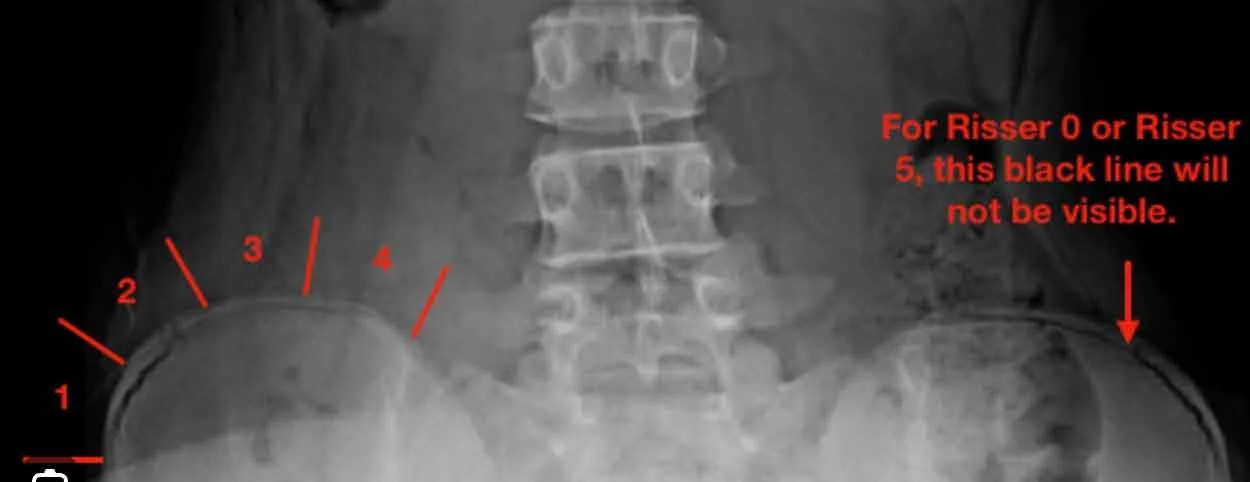

The first, the Risser sign, determined by looking at the X-ray of the hip bone, has been used since 1958.

Risser Sign via X-ray

The grading system for Risser is 0–5, with 0 being the least skeletally mature and 5 being fully skeletally mature. This system was used as standard practice until 2011, when Sanders simplified skeletal maturity scale was developed and became the new status quo of measuring skeletal maturity.